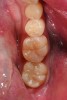

A 48-year-old patient presented with an old, failing Class I alloy restoration and showed recurrent decay on the lower molars (Figure 9). After the existing alloy was removed, the remaining tooth structure was evaluated. It was determined that despite the significant extent of caries present, it would be possible to perform a minimally invasive procedure using an injectable composite resin and an RMGI (Figure 10).

After removing the infected dentinal layer, a caries-detection stain was used to determine if further tooth removal would be necessary. On removal of all infected dentin, a chlorhexidine gluconate swab (CAVITY CLEANSER™ 2% Chlorhexidine Digluconate, BISCO, Inc.) was used to remove any surface bacteria on the prepared site. Next, a polyacrylic acid scrub was performed for 20 seconds to condition the dentin surface. An RMGI (GC Fuji II LC) was sculpted and light-cured to cover the affected and unaffected dentin.4,13,18,19 After the RMGI liner was fully cured, a micropreparation diamond bur (830RM.FG.009, Komet USA) was used to refine the internal form of the preparation. Marginal beveling to a 45° taper was completed along the cavosurface of the final tooth preparations.15

A dentinal adhesive resin was used to further seal the cavity preparation. Using a seventh-generation adhesive (ALL-BOND UNIVERSAL), a polymer chain union was created between the composite resin and RMGI.16 Following proper placement of the adhesive resin, an injectable composite resin (G-ænial Universal Flo) was placed over the RMGI, causing intimate union between the materials. An incremental build-up technique using the injectable composite resin was then easily employed to anatomically reconstruct the tooth.21-23 Because the selected resin has an excellent depth of color, a natural-looking result was achieved with a single shade of resin.24,25

Accurate contouring and margination was achieved using Q-Finisher composite resin finishing burs for final finishing. A composite finishing (H247UF.314.009, Komet USA) (H274Q.314.018, Komet USA) was used to develop initial occlusal anatomy, after which a 30-fluted finishing bur refined the occlusal surface smoothness. Finally, using one-step microdiamond-infused finishing points (C9479, Komet USA) and a microdiamond polishing paste, a natural-looking finish and polish was achieved (Figure 11).27